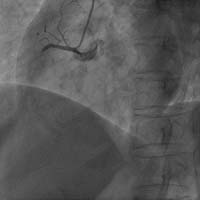

Carto三維定向標測系統(tǒng)指導下房顫射頻消融術(shù)